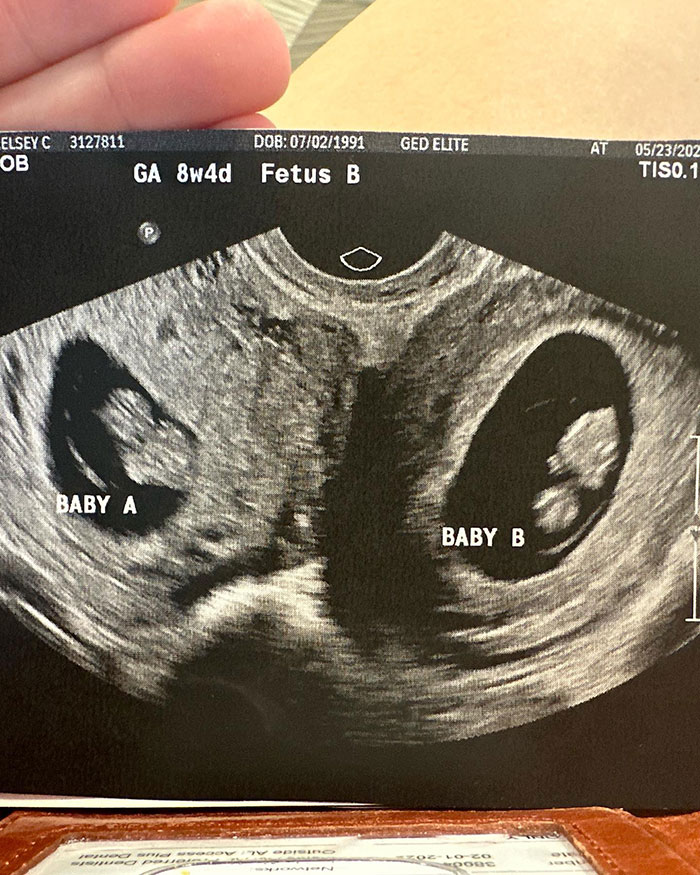

Kelsey Hatcher has a rare condition where she lives with a double uterus, expecting a child in each of the organs.

The expecting mom from Alabama, USA, was in fact born with two functional uteri that each have their own cervix.

Kelsey Hatcher is expecting two girls, pregnant in two sets of uterus, a rare condition she was born with

Dr. Richard Davis, a specialist in high-risk pregnancies at the University of Alabama, told the news outlet: “A double cervix or double uterus is way under 1%, maybe three per 1,000 women might have that.

“And then the probability of you having a twin in each horn is really crazy.”

Upon discovering her pregnancy last spring, followed by a first ultrasound, Kelsey shared the amazing news that she was not only pregnant but expecting babies in both organs, with her husband Caleb.